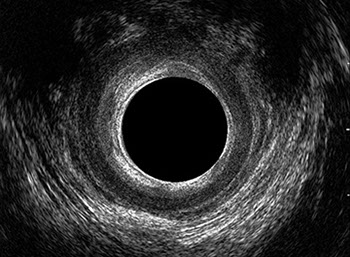

L’ecografia transanale è un esame diagnostico per immagini che consiste nell’introduzione di un trasduttore ad ultrasuoni. Le immagini qualitativamente migliori del canale anale sono ottenute usando un trasduttore rotante, montato in un manipolo rigido, che fornisce un’immagine a 360°. Con le apparecchiature più moderne è anche possibile ottenere immagini tridimensionali.

L’ecografia transanale permette di distinguere la sottomucosa che riveste il canale anale, lo sfintere anale interno, e lo sfintere anale esterno.